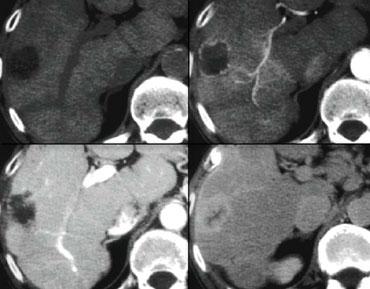

Trước tiên hãy quan sát các hình ảnh bên trái và mô tả những gì bạn thấy. Sau đó tiếp tục đọc.

Tổn thương này chắc chắn có một số đặc điểm của u máu như ngấm thuốc dạng nốt trong thì động mạch và ngấm thuốc lấp đầy dần trong thì tĩnh mạch cửa và thì cân bằng.

Tuy nhiên, trong thì tĩnh mạch cửa, mức độ ngấm thuốc không sáng bằng mức độ ngấm thuốc của tĩnh mạch cửa.

Kết luận phải là tổn thương này không tương đương hồ máu ở tất cả các thì, do đó không thể là u máu.

Vì vậy, ngấm thuốc lấp đầy dần là một đặc điểm không đặc hiệu, có thể gặp trong nhiều tổn thương khác như di căn hoặc các khối u gan nguyên phát như ung thư biểu mô đường mật.

Sự ngấm thuốc thì muộn trong tổn thương này là do mô xơ trong ung thư biểu mô đường mật và là đặc điểm đặc trưng của các khối u này.